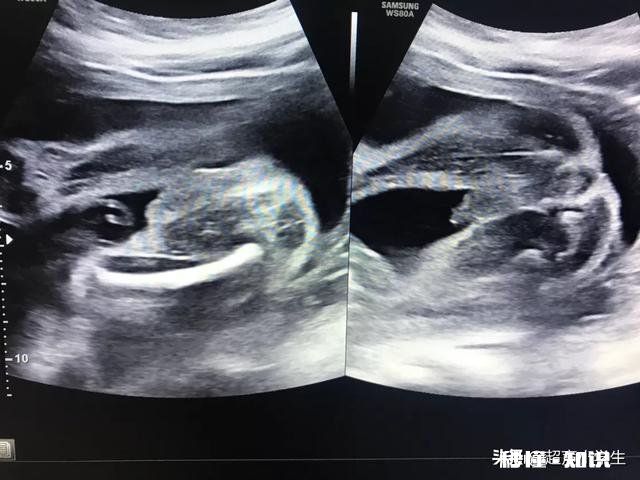

文章插图

怀孕生男孩胎心率是每分钟多少下?我又找出大宝当年的孕妇保健手册看了下,胎心率基本集中在146次左右,是大于140次/分的 。

我家二宝的胎心率是这个情况:胎心率检测仪检测的数据在140-156次/分之间 。B超检测的胎心率在139-158次/分之间,6次B超只有一次是139次/分,其余均在150次/分之上 。总之,二宝的胎心率是大于140次/分的 。

从我家这两个男宝的情况来看,就说明流传的胎心率看男女的说法是不靠谱的 。